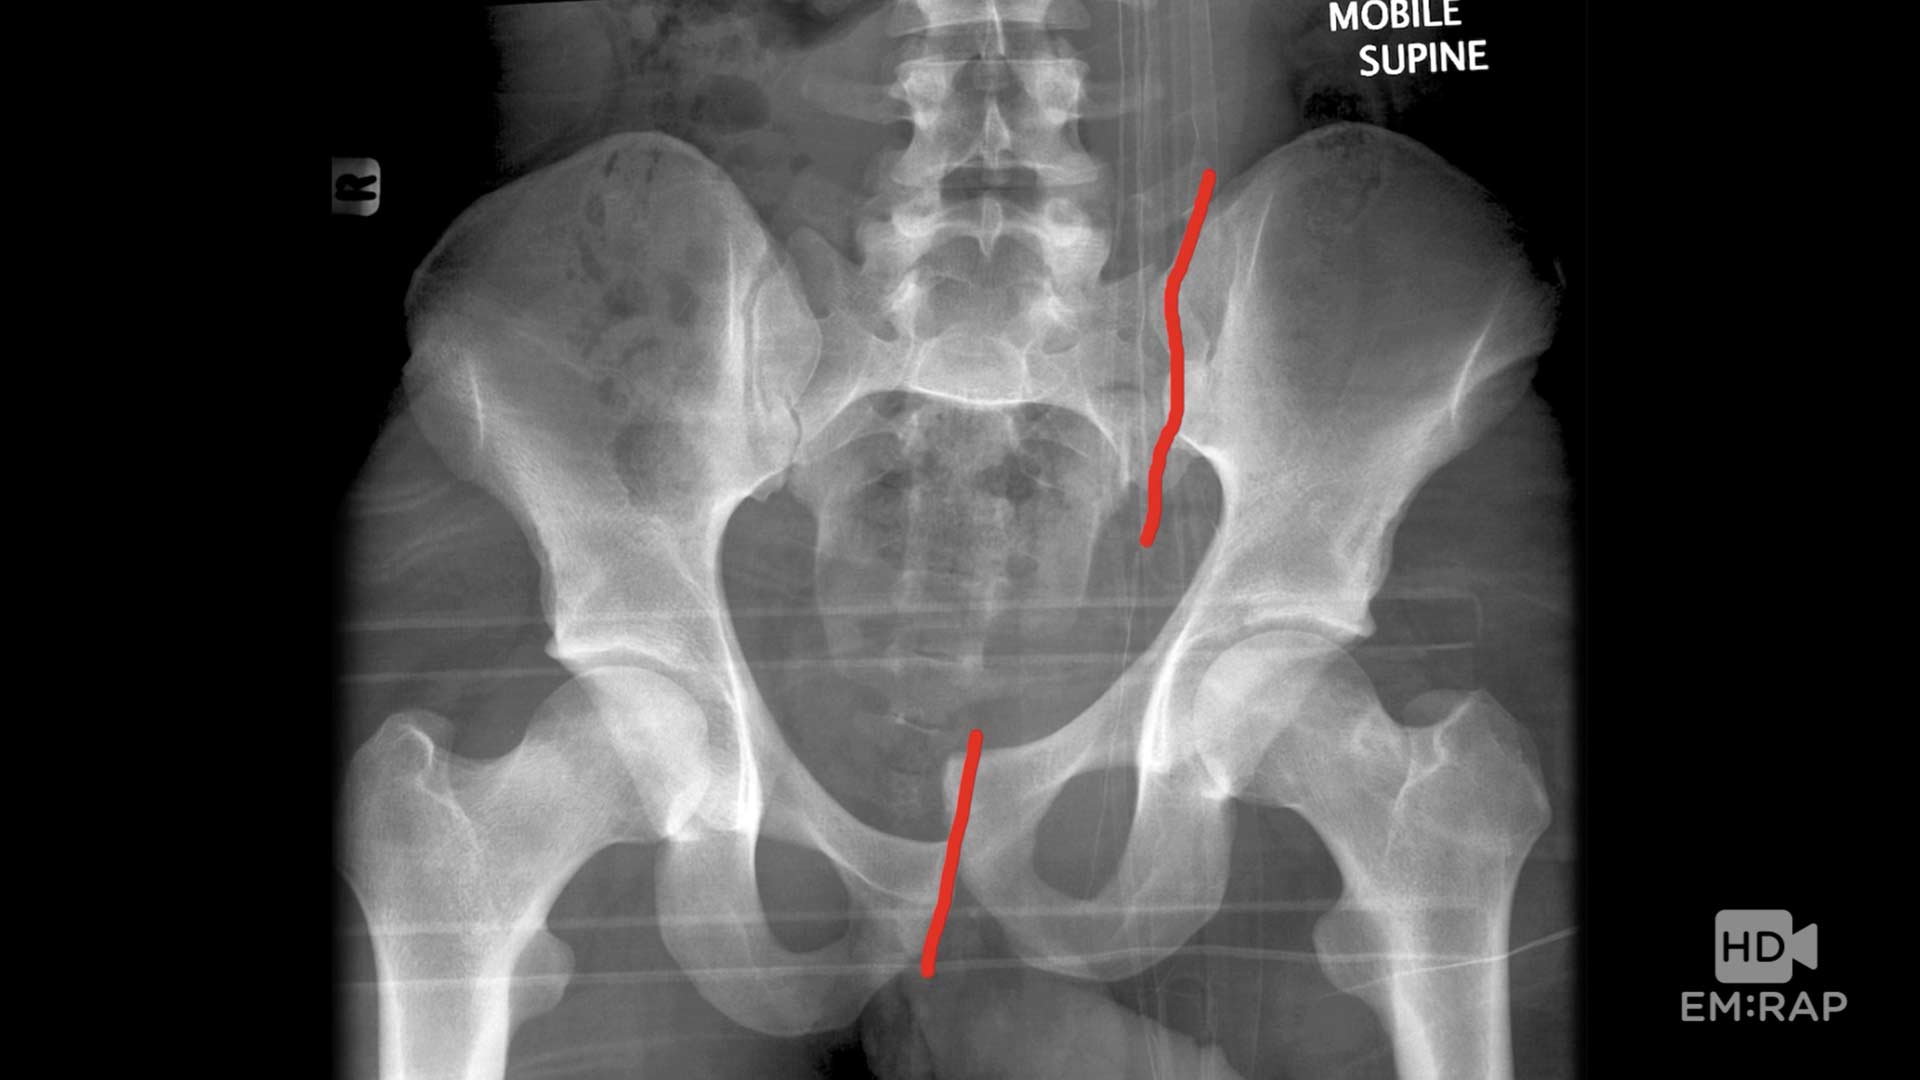

شکستگی های حفره لگن نوعی از شکستگی های لگن هستنـد که همانطور که از نامشان پیدا است در حفره ایی واقع در لگـن خاصره ایجاد می شوند علت این شکستگی ها معمولا“ تصادف اتومبیل یا سـقـوط از بلندی است. غالبا این شکستگی نیاز به عمل جـراحـی دارنـد. بعضی از شکستگی ها نیز با کشش و گذاشتن وزنه درمان مـی شوند.